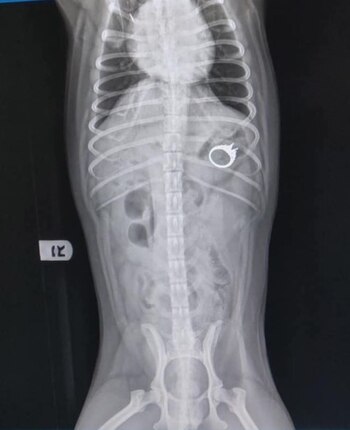

“Fui al veterinario, pensando que no había forma de que se lo hubiera comido. Pero solo quería estar segura. Pero el veterinario me dijo que el anillo estaba ahí. Yo estaba en shock. Cuando lo vi en la radiografía, estaba totalmente incrédula. Una cosa es escuchar al veterinario decir que está en su estómago, y luego verlo tan claramente lo hizo realidad”, expresó.

Fue entonces que le explicaron los siguientes pasos: el anillo era muy grande para poder pasar de manera natural, e incluso había un riesgo muy grande de muerte, por lo que tuvo que ser sometido a una endoscopia bajo anestesia general.

“Dijeron que es demasiado grande para pasar de forma natural, y debido a que tiene bordes afilados, podría perforar su interior y posiblemente matarlo. Mencionaron que una endoscopia era mucho más segura que la cirugía, por lo que hicieron el procedimiento y afortunadamente Patrick estaba bien. No tiene idea del drama que causó”, agregó.